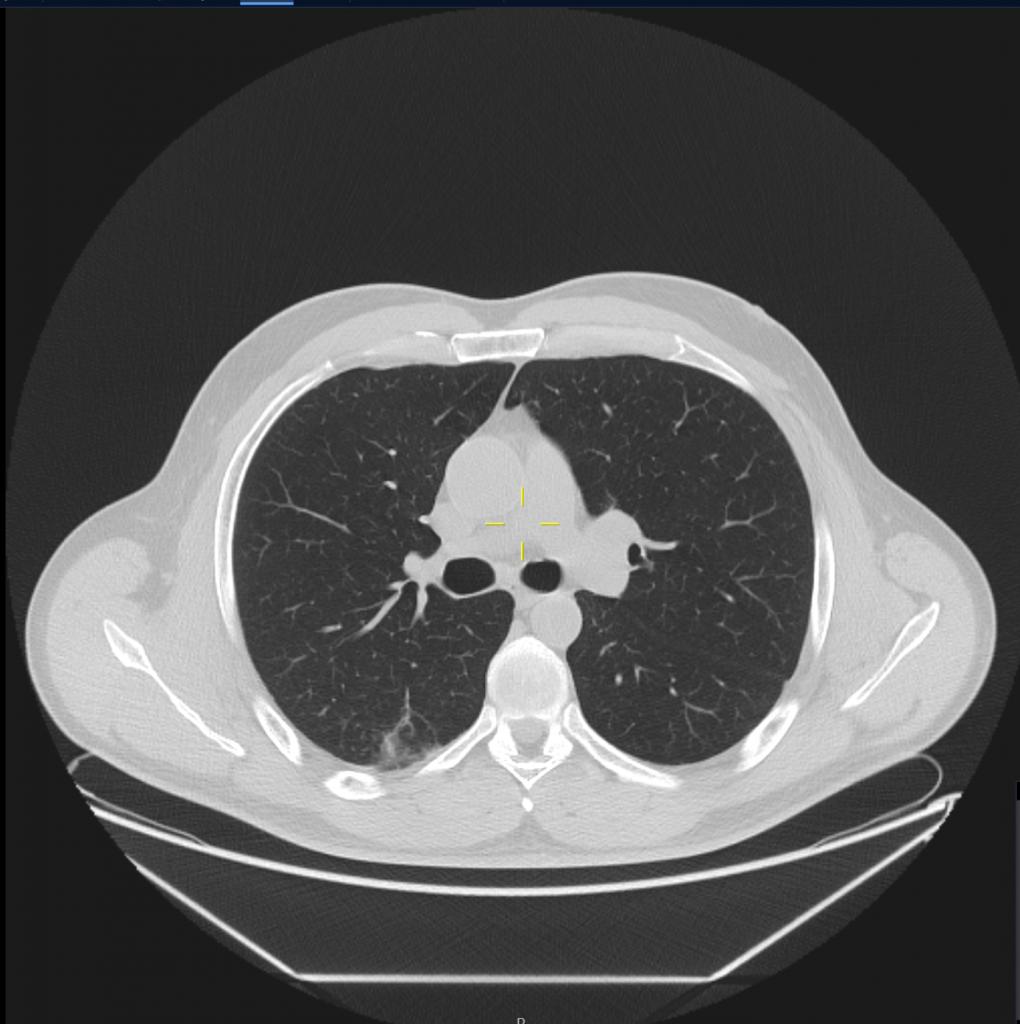

Ņemot vērā, ka SARS-CoV-2 skar daudzus pacientu orgānus, darba ietvaros pacientiem, kuri pārslimojuši COVID-19 infekciju tika veikti krūšu kurvja datortomogrāfijas bez kontrasta izmeklējumi ar 64 slāņu datortomogrāfu ar standarta izmeklēšanas protokolu, un augstas rezolūcijas izmeklējumu potenciāli bojāto plaušu audu rajonam, visiem pētījuma dalībniekiem veikti MR ar 3 Tesla stipru magnētiskā lauka aparātu vēdera dobuma orgāniem, lai diagnosticētu iespējamos bojājumus parenhimatozos orgānos, izmantojot standarta izmeklēšanas sekvences (FSE T2; FSE T1; SPGR in phase, out phase) un difūzijas uzsvērto attēlu (DWI), ar dažādām pieaugošām b vērtībām (50; 200; 800; 1000; 2000), kā arī šķietamā difūzijas koeficienta noteikšanu (ADC). Veikti US izmeklējumi vēdera dobuma orgāniem, limfmezgliem, lai diagnosticētu dažādus COVID-19 izraisītu aknu, nieru un liesas bojājumus, izmantojot standarta izmeklēšanas režīmus (B režīms, krāsu doplerogrāfija) un papildus veikta multiparametriska aknu izvērtēšana ar elastogrāfiju, izmantojot US šķērsviļņu metodi (2D SWE), vērtējot padziļināti aknu fibrozes un viskozitātes pazīmes kvantitatīvi, kā arī steatozes pakāpi. Radioloģiskā atradne tika korelēta ar laboratorisko atradi un klīniskiem datiem.

Projekta ietvaros atklāts, ka COVID-19 pārslimojušiem ir vērojamas izmaiņas aknu viskozitātē, elasticitātē, apstiprina pārciestu aknu bojājumu, kas konstatējams vēdera dobuma utrasonogrāfijas un multiparametrisku aknu izvērtēšanas metodē un būtu ieteicams kā skrīninga izmeklējums seku parādību izvērtēšanā ari turpmāk. Plaušu atrade lielākoties neuzrādīja specifiskas seku pazīmes, kas liecina par plaušu audu augstu atveseļošanās potenciālu pēc pārslimošanas. Citos parenhimatozos izvērtētajos orgānos, limfmezglos specifiskas seku pārmaiņas netika konstatētas.

Plaušu izmaiņu izvērtēšana datortomogrāfijā, kvantitatīva plaušu apjoma novērtēšana